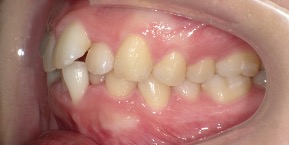

29歳女性のビフォーアフター

| 診断 | 叢生(デコボコがある状態)、過蓋咬合 |

| 治療方針 | インビザラインシステムにて主にIPR(歯と歯の間をわずかに削合してスペースを獲得する方法)を組み込んだ動的矯正治療を行い、叢生を改善後、保定を行う。臼歯部の咬合関係はプランの関係上維持して叢生と前歯部の咬合改善を目指した。 |

| 治療費 ※ | 60万4千円(診断、型取り、PMTC、保定装置を含む料金) |

| 治療期間 | 1年5か月 |

| リスク | 1日20時間以上マウスピースを使用できない場合、歯が動かない可能性がある。装着時や食事時に痛みを伴う。歯肉退縮や虫歯になるおそれがある。また、指導通りに装着できていない場合や適切なブラッシングが出来ていないとそのリスクが高くなる。歯根が短くなることがある。ごくまれに歯の神経が損傷してしまうことがある。過去にぶつけたり深い虫歯治療をしたことがあるとそのリスクはやや高くなる。矯正後には保定装置が必要。適切な使用ができない場合、後戻りの原因となる。将来的に歯並びが動いて再矯正が必要な場合がある。親知らずが正常に生えていない場合、その可能性がやや高くなる。 |